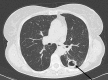

Mycobacterium yongonense in Pulmonary Disease, Italy

Source:Emerg Infect Dis. 19(11):1902-1904.